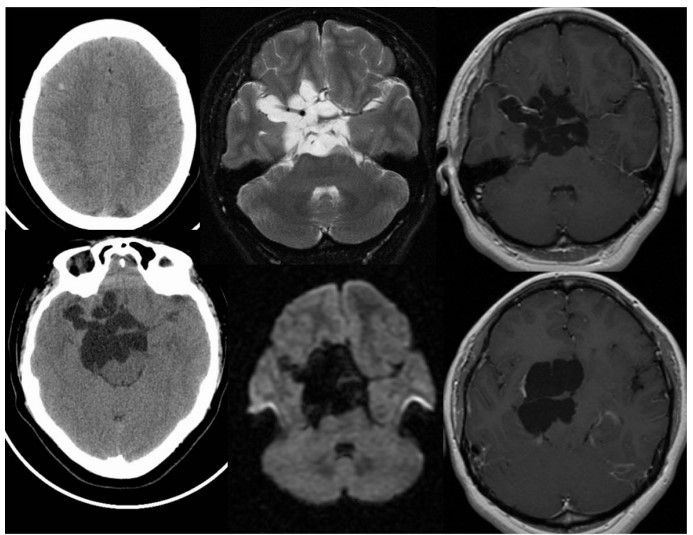

- In a few cases, it may reappear as a calcified scar (Calcified Stage). Sometimes, uncontrolled parasite growth in the subarachnoid space leads to the formation of large parasite clusters resembling a bunch of grapes (racemose neurocysticercosis) (Fig. 2)

Fig 2: Racemose form of NCC. Multiple CT and MR images demonstrate multilobulated and multiseptated CSF signal/density structures within the suprasellar cistern, associated with localised mass effect and a few linear areas of peripheral enhancement.